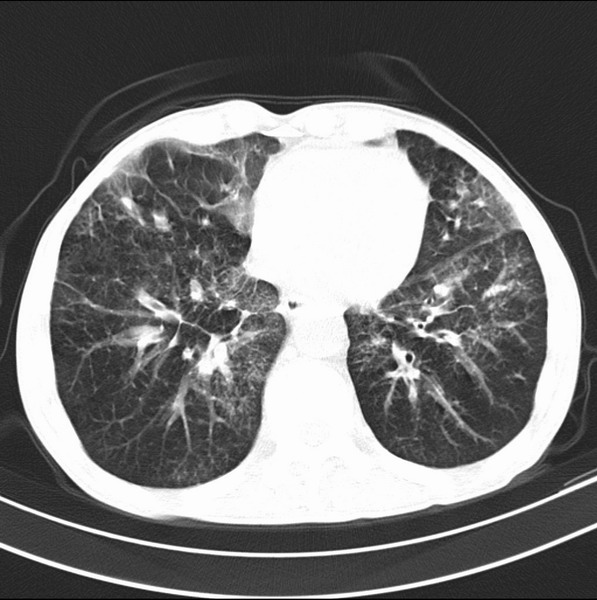

标题: CT19600:能否诊断为转移?

女、55

3年前盲肠癌、一年半前诊断膀胱癌,现在呼吸困难,临床考虑为肺转移

请问胸部ct如何诊断?能否排除淋巴管炎,纵隔窗没有问题。

考虑间质性病变,癌性淋巴管炎可能.

转移,癌性淋巴管炎。

炎性并间质纤维化

炎性并间质纤维化,请询问病史,如用过平阳霉素或其他化疗药.可能为药物引起的间质纤维化.

考虑间质性病变,癌性淋巴管炎可能.支持!

支持考虑间质性病变,癌性淋巴管炎可能.